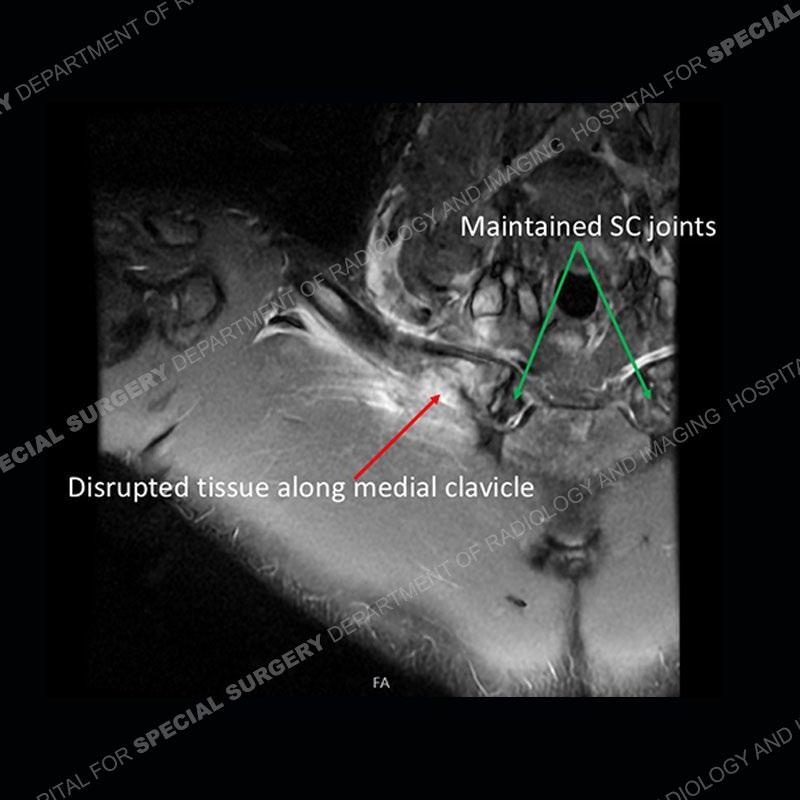

Subsequent imaging of the chest shows disruption of tissue along the medial aspect of the right clavicle and a deep insinuation of the bone along the medial aspect of the right clavicle. This is made more conspicuous with comparison to the left side. The edema pattern of the clavicle and the edema/hematoma of the subclavius persist.

The costoclavicular ligament (rhomboid ligament) extends from the undersurface of the clavicle to the first rib. The ligament attaches to the clavicle approximately 1cm lateral to the SC (sternoclavicular) joint. Injuries to the ligament are typically in the setting of an injury to the SC joint. Isolated injuries without SC joint injury are extremely uncommon with limited case reports in the literature.

The attachment of the ligament to the clavicle may have a normal variant with a deep fossa termed a rhomboid fossa. If this variant and its location are not known, it could mimic erosion or destruction of the bone. Adding more confusion is that the variant does not need to be bilateral or symmetric (as in this case where it is unilateral).